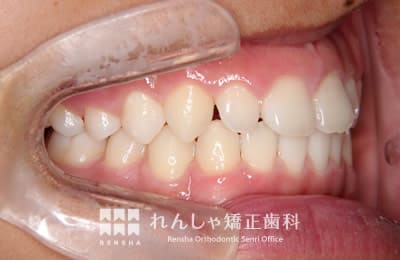

中高生

永久歯列はほぼ完成してしますが、歯列を側方だけでなく後方へも拡大し、埋まっていた右上奥歯を引っ張り出しています。

| 主訴 | 埋まったままでてこない歯がある |

|---|---|

| 診断名 | Angle Class II 小臼歯の埋伏と叢生を伴う上顎前突 |

| 初診時年齢 | 13歳5か月 |

| 装置名 | マルチブラケット装置 |

| 抜歯非抜歯 | 非抜歯 |

| 治療期間 | 2年3か月 |

| 費用の目安 | 約82万円+消費税(検査料金、都度の処置費用等も合わせた総額) |

| リスク副作用 | 歯の移動に伴う軽微な歯根吸収、歯槽骨吸収、歯肉退縮(本症例では軽度の歯根吸収を認めた)、矯正器具装着中のカリエスリスク増大(本症例ではカリエス発生無し) |